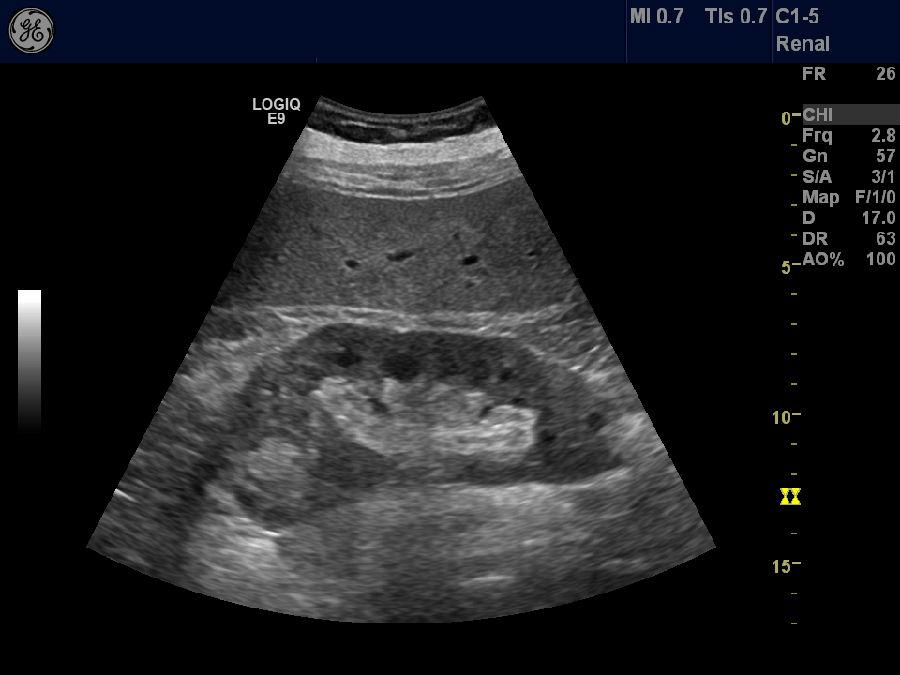

慢性肾脏病(Chronicrenaldisease,CKD)是指各种原因引起的肾脏损害或GFR,肾脏损害包括肾脏功能异常(如蛋白尿,或尿沉渣异常,如畸形红细胞)或影像学研究中指出的结构异常。

在研究中我们还发现,不管是CKDND还是HD、PD患者,他们的血清硒水平均处在正常偏低水平,与HC组相比,差异有统计学意义,这与研究结果一致。此外,我们还发现血硒与SCr呈负相关,这说明硒在一定程度上参与了CKD的发生与发展,对肾功能有一定的保护作用,低硒水平可能诱发或加重肾功能衰竭的进展。研究也提示,低硒水平可增加患者死亡风险。

由于肾脏是健康人排泄硒的主要途径,CKD状态势必会影响体内的硒水平。目前研究提示,CKD患者体内硒水平普遍偏低,这一观察结果可能是由于:CKD患者特别是ERSD患者长期处于厌食、营养不良状态,这就使摄入的含硒食物不足。